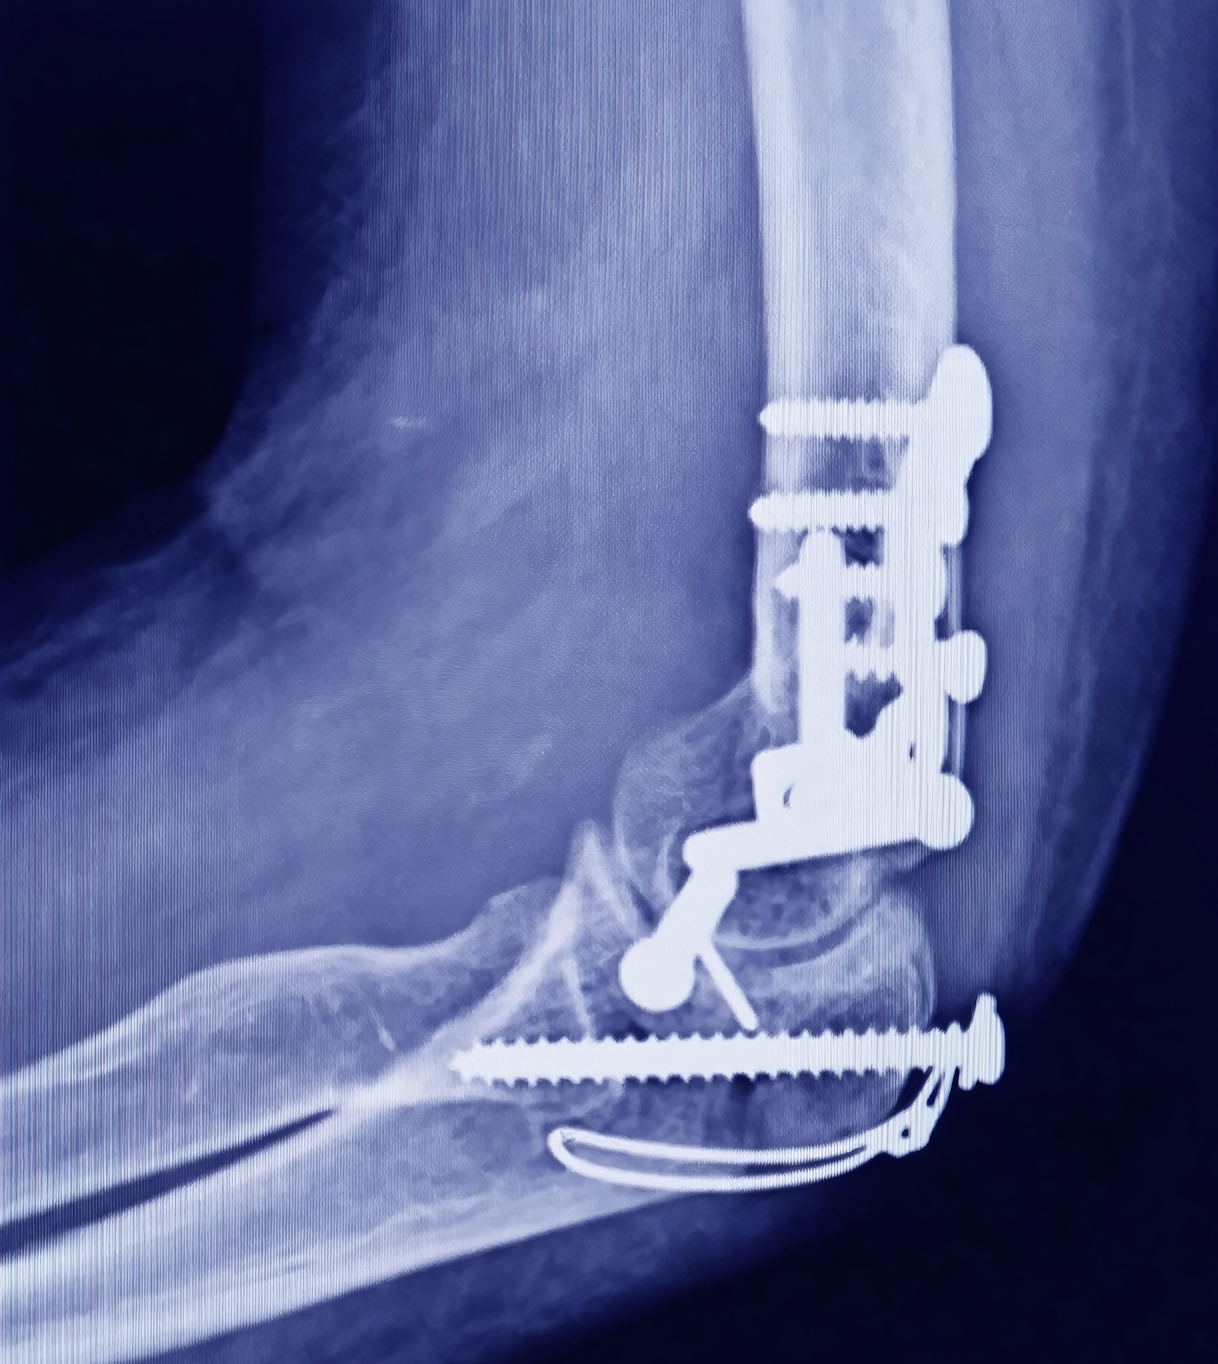

Después